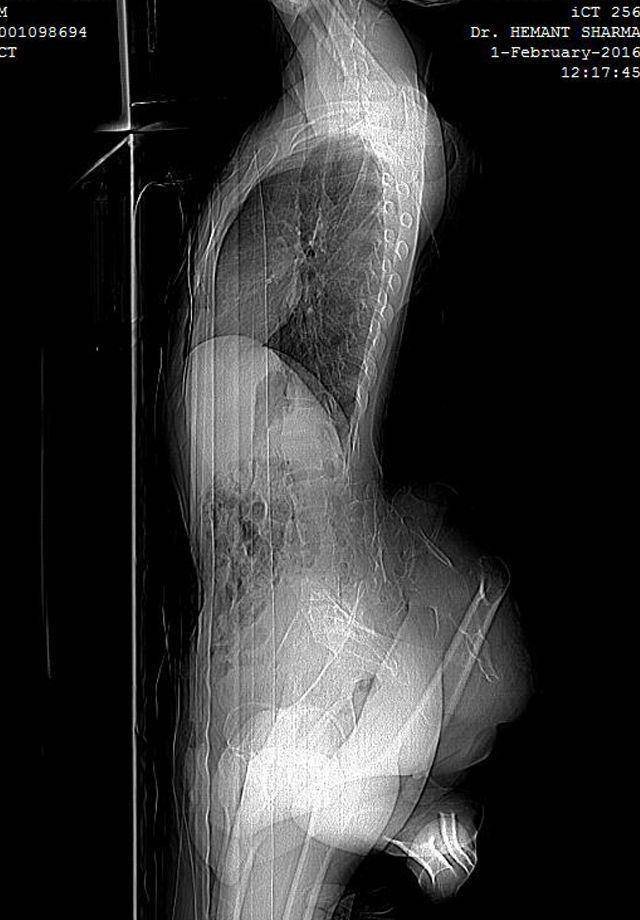

22-летний Арун Кумар из индийского штата Уттар-Прадеш родился с двумя лишними ногами, растущими из его поясницы. Одна из них неразвита, вторая - постоянно согнута в колене. Паренек живет без какого-либо лечения на протяжении 15 лет, и вот теперь, благодаря социальным сетям, его случаем заинтересовались врачи.